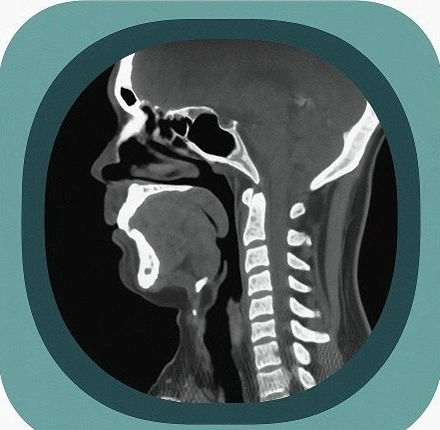

Explore full-body CT anatomy in 3 planes. Our high-resolution, carefully labelled images reveal micro-anatomy—ideal for radiologists, radiographers and surgeons.